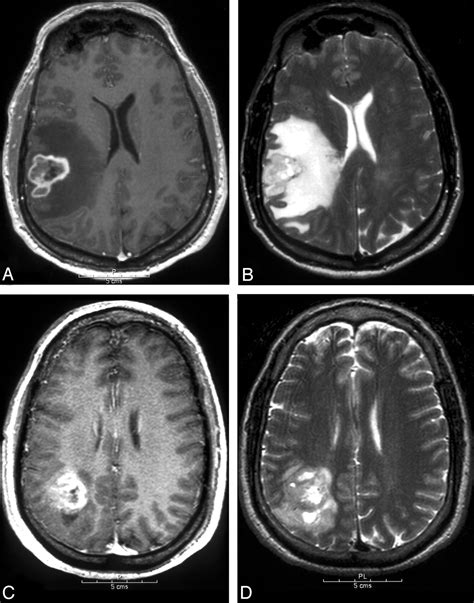

The journey toward a formal diagnosis usually begins with a neurological examination followed by advanced imaging. Physicians rely on several diagnostic tools to map the tumor’s size, location, and relationship to vital brain structures. Magnetic Resonance Imaging (MRI) with contrast remains the gold standard for visualizing these growths. In many cases, specialized sequences such as spectroscopy or perfusion imaging are used to differentiate between tumor tissue and postoperative changes.

• high grade glioma MRI